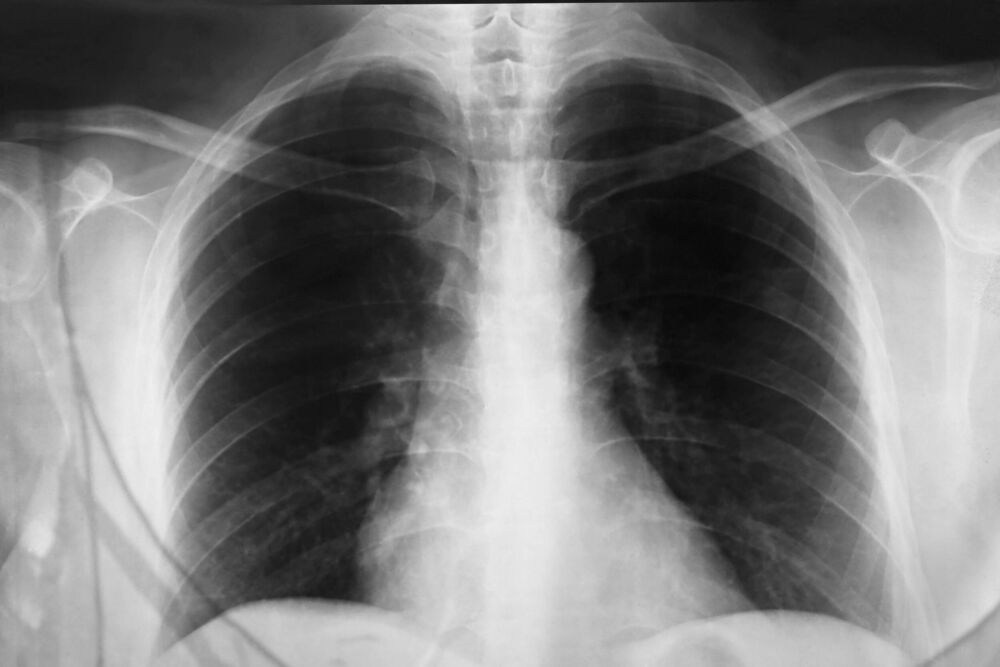

Ljekari naglašavaju da ovakav kašalj, iako neugodan, ne bi trebao trajati duže od tri sedmice. Ako potraje duže, kažu, potrebno je odmah obaviti detaljan pregled pluća kako bi se isključili ozbiljniji uzroci. Posebno upozoravaju da je ključno u ranoj fazi otkriti razlog kašlja kako bi se spriječile komplikacije i kako bi terapija bila što efikasnija.

Ljekari poručuju da svako ko ima dugotrajan ili neuobičajen kašalj treba da se javi stručnjaku, jer rana procjena može spriječiti ozbiljne posljedice. Posebno je važno obratiti pažnju ako se javljaju otežano disanje, zviždanje u grudima ili bol u prsima.Uz pravilnu brigu, kontrolu okruženja i stručni savjet, moguće je značajno smanjiti tegobe i izbjeći komplikacije koje nastaju kada se simptomi zanemare.